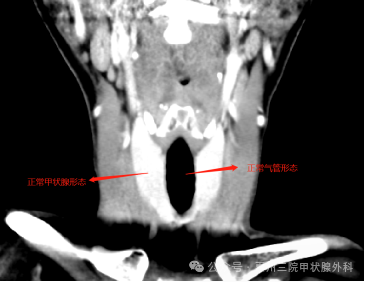

正常人的頸部CT